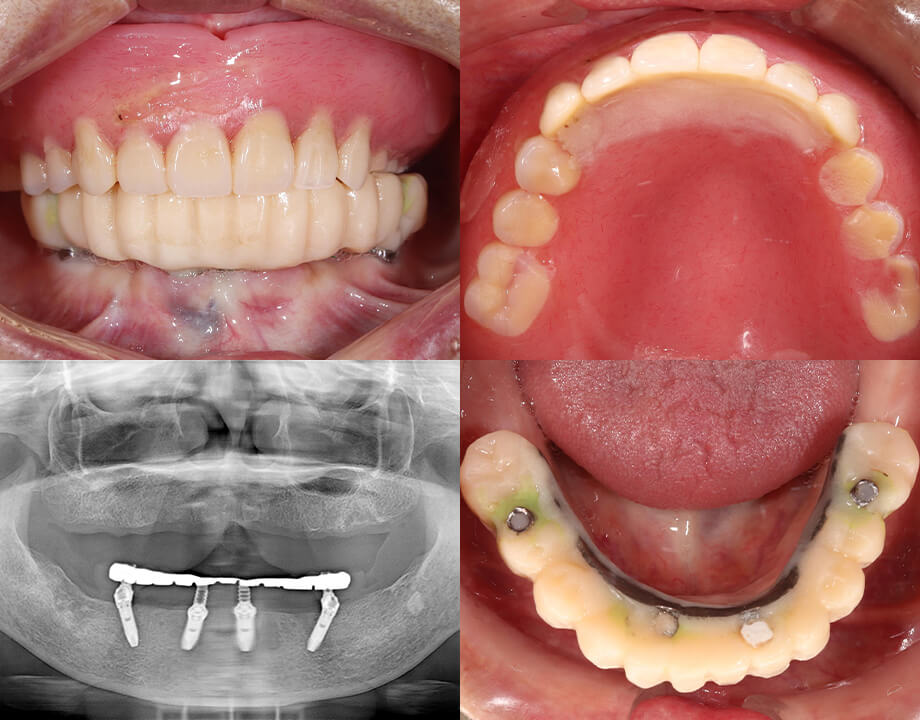

Case 02インプラント

モノリシックジルコニア